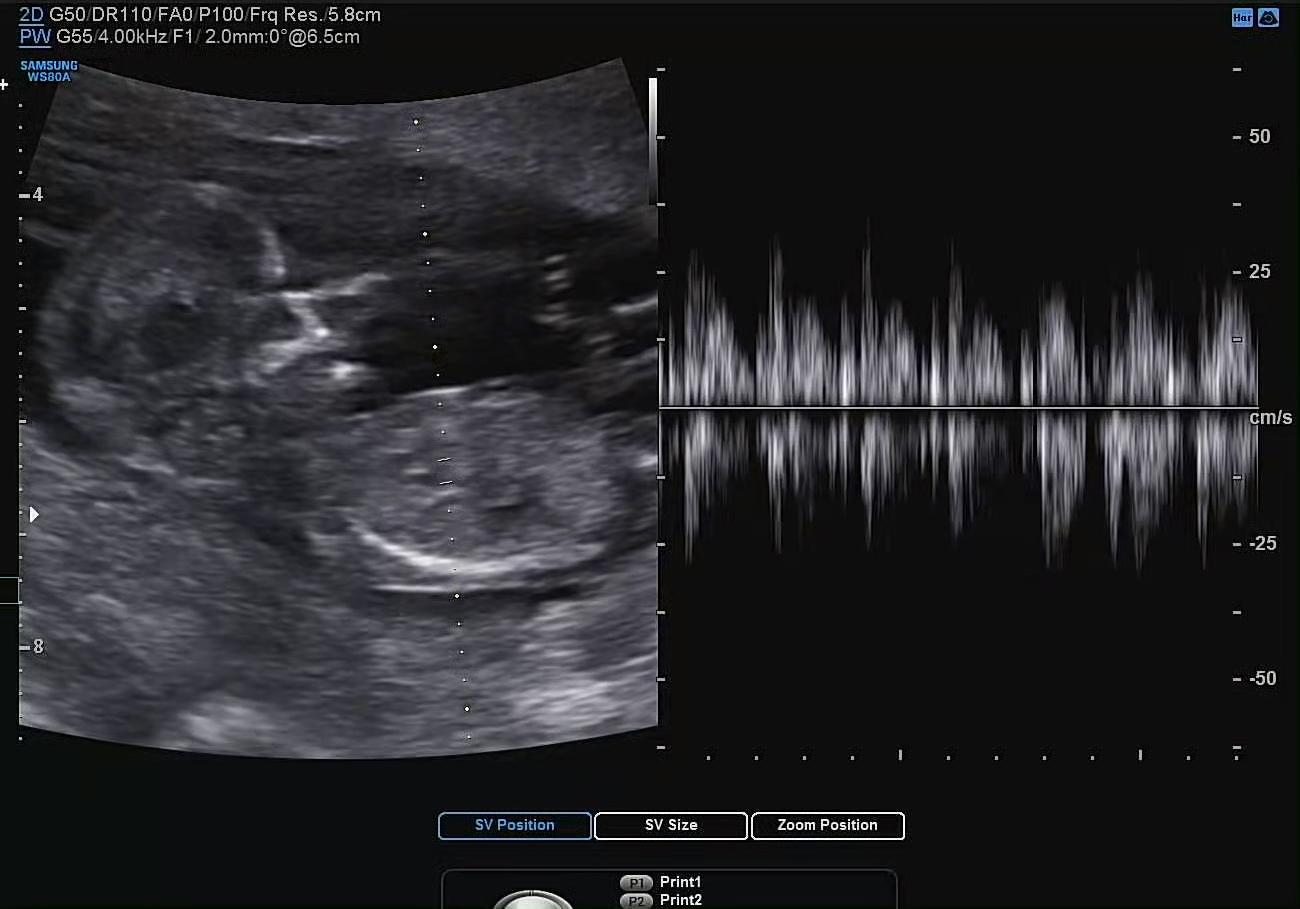

심박수도 9주 때와 비슷하게 160으로 잘 나왔다. 성인보다 2배 정도 빠른 심박수를 보이는 태아. 현재 6cm 정도의 작은 크기임에도 불구하고 손발과 심장이 모두 존재한다는 게 정말로 신기할 따름이다.